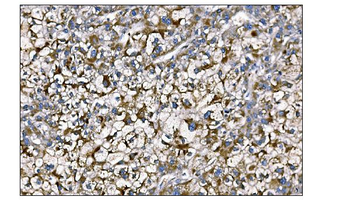

IHC staining of FFPE human colon carcinoma with MerTK antibody (clone TPKR-1). HIER: boil tissue sections in pH9 10mM Tris with 1mM EDTA for 10-20 min and allow to cool before testing.